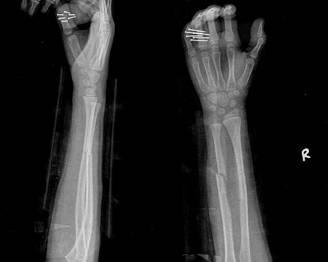

摘要:最新尺橈骨融合方法展現(xiàn)骨頭間的奇妙和諧與友情力量。通過先進(jìn)的醫(yī)療技術(shù),尺骨和橈骨之間的融合得到顯著改善。這種方法不僅提高了治療效果,還展現(xiàn)了人體骨骼之間的和諧關(guān)系。憑借友情和信念的力量,醫(yī)學(xué)界不斷突破,為患者帶來福音。

經(jīng)過醫(yī)生的診斷,小明被確診為尺橈骨融合,這是一種骨骼疾病,會導(dǎo)致尺骨和橈骨無法正?;顒樱牭竭@個(gè)消息后,小明和他的朋友們都感到有些緊張和害怕,但他們并沒有放棄,而是選擇相互鼓勵(lì),共同面對這個(gè)挑戰(zhàn)。

在醫(yī)生的介紹下,他們了解到了一種最新的尺橈骨融合治療方法——通過微創(chuàng)手術(shù)進(jìn)行骨骼融合的新技術(shù),這種方法不僅減少了手術(shù)風(fēng)險(xiǎn),還能更快地恢復(fù)活動能力,雖然小明感到害怕,但他的朋友們一直陪伴在他身邊,給予他勇氣和力量。